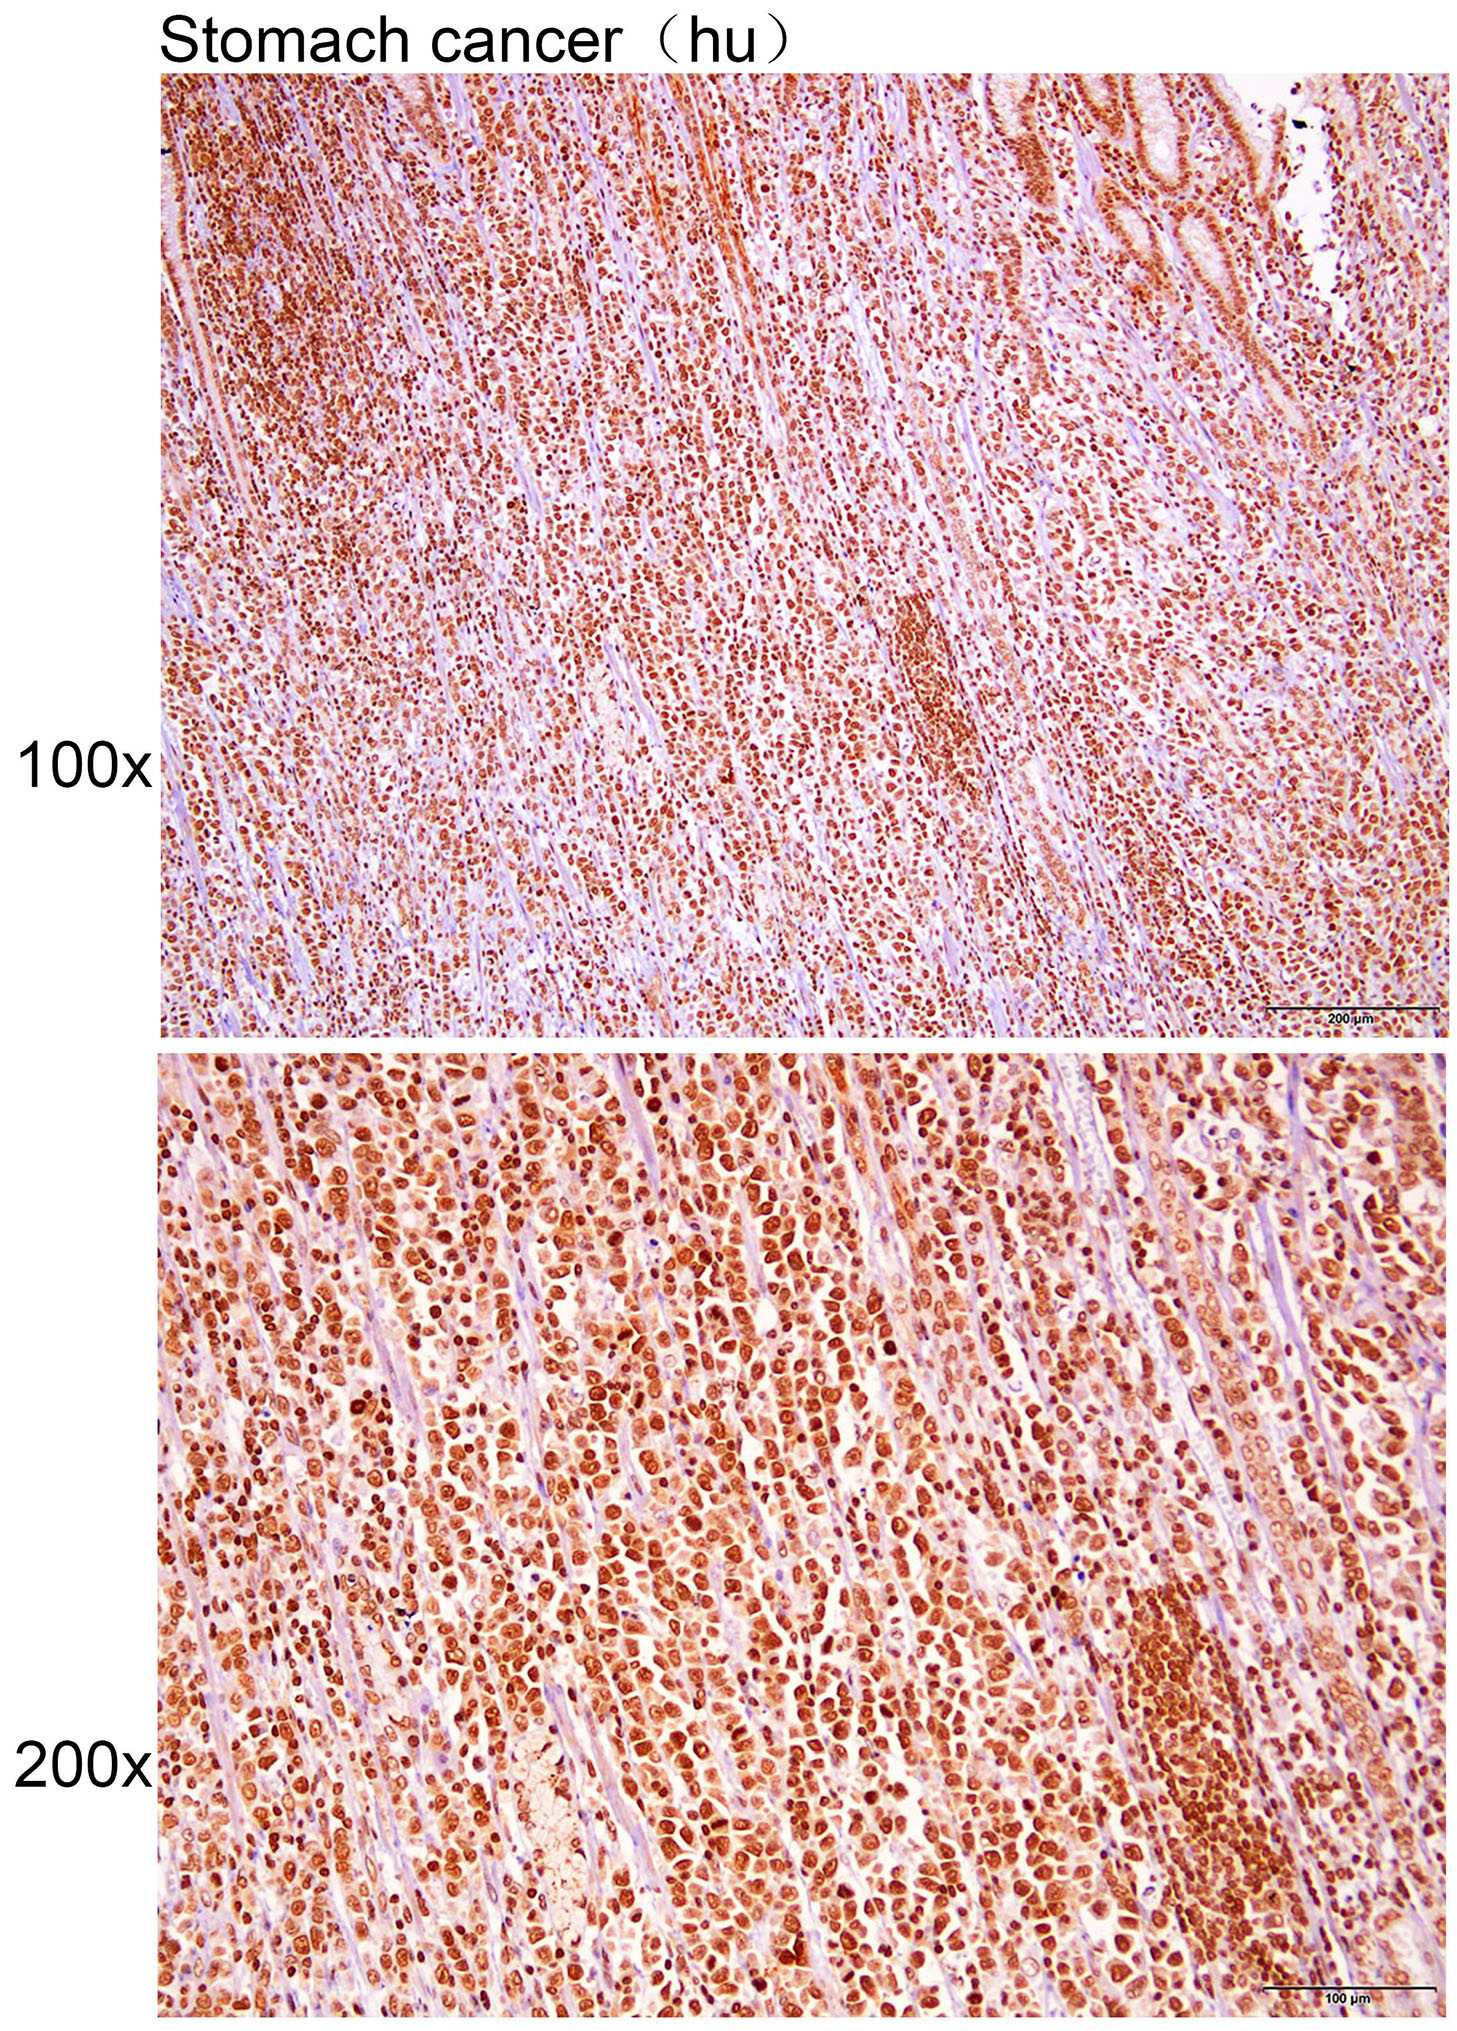

Immunohistochemistry of?paraffin-embedded?Human stomach cancer with Gli2 antibody diluted at 1:200